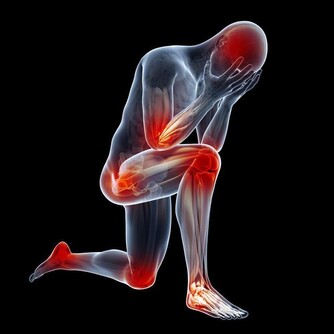

長期過量吃糖,會帶來這些危害:傷牙、長胖、跟骨頭搶鈣、加速皮膚老化、誘發多種疾病(痛風、糖尿病、心腦血管等慢性病)。